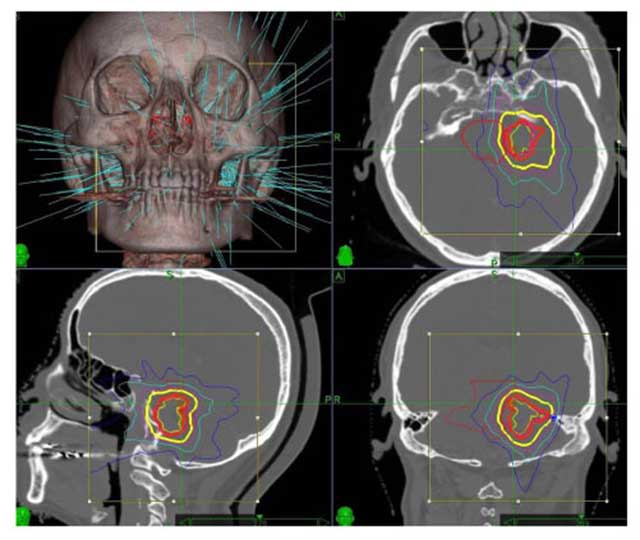

數碼導航刀放射治療

數碼導航刀放射手術適用於3厘米以下的腫瘤或手術後殘餘的腫瘤,老年、體質差的病人也適用。數碼導航刀放射治療相對風險比較小、康復快、治療時間短,一般3至7天便可。其治療效果與射線照射劑量有一定相關性,但腫瘤有囊性變化、腦幹受壓明顯者不建議此方法治療。其治療的原理是通過高能量射線照射殺死腫瘤細胞,或控制腫瘤細胞的生長。放射治療後短期內,腫瘤會有水腫、擴大的可能,因此術後短期內可能需要脫水降顱壓治療。醫學文獻分析結果顯示,數碼導航刀治療聽覺神經瘤的腫瘤控制率為85至100%,聽力保留率為60%,併發症發生率為5.6%。